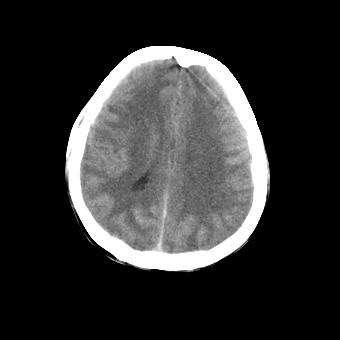

标题: CT16478:男 头晕 恶心 呕吐 [打印本页]

标题: CT16478:男 头晕 恶心 呕吐

2.纵裂密度增高,部分脑回密度似乎也增高,蛛网膜下腔出血。

脑水肿?建议短期复查。

脑水肿?蛛网膜下腔出血?------病史?

弥漫性脑肿胀,建议增强检查

脑水肿?建议短期复查

[quote]以下是引用叶子123在2008-11-13 9:55:00的发言:[br]患者因煤气中毒入院,临床及ct均诊断一氧化碳中毒性脑病[br][br]